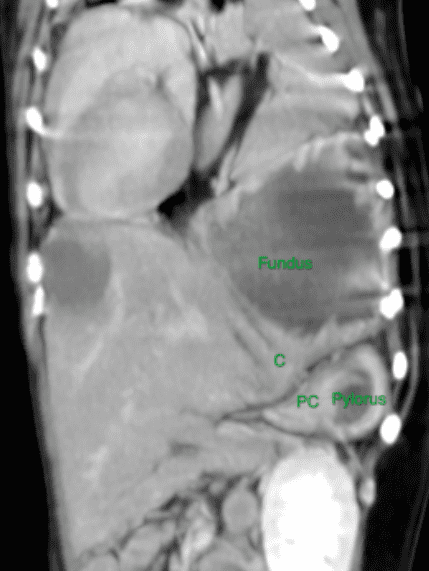

“She was anaesthetised and a CT scan was performed which confirmed the diagnosis of a congenital diaphragmatic hernia.

“These defects are often overlying the stomach, which can then enter the thorax and fill with air compressing the surrounding lungs and stopping the dog being able to breathe effectively.

“Sally was rushed to surgery where her stomach and spleen were placed back into her abdomen and the diaphragmatic defect was closed after a chest drain was placed.